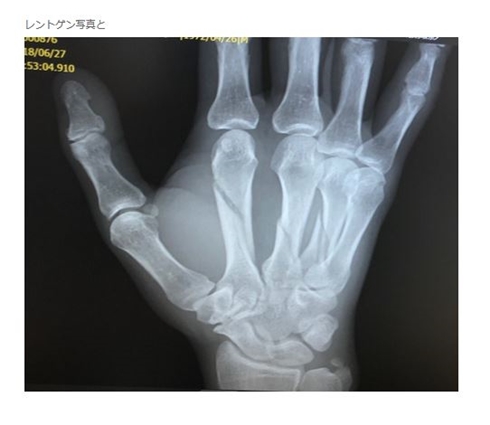

「バキッって音がして瞬間的に折れたと思いました」と確信を抱きつつ病院に行きレントゲンを撮ると、1本どころか人差し指と中指、薬指につながる甲の骨が3本骨折。担当医から「めちゃくちゃ折れてます」とバッサリ診断されたことを明かしています。どっからどう見てもめちゃくちゃ折れてる。

骨折部分がばっちり分かるレントゲン写真(画像は品川祐オフィシャルブログから)